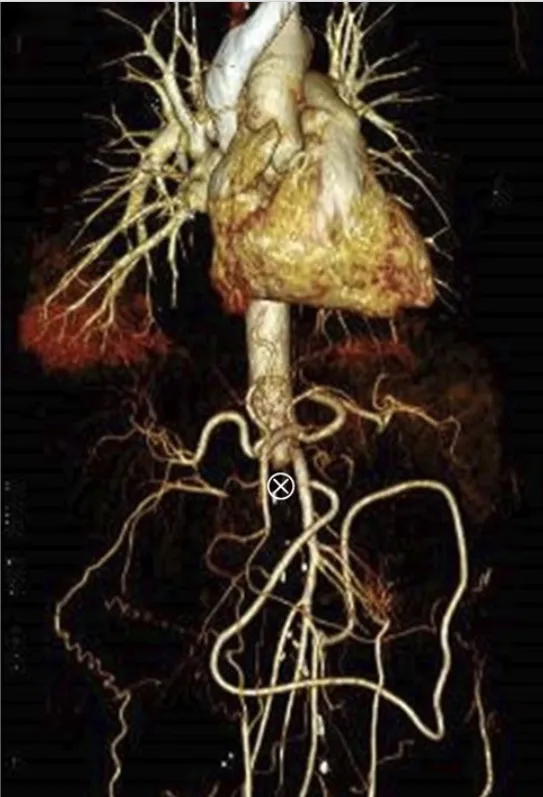

IRA + Icterícia: Um Caso que Exige Investigação Detalhada